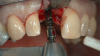

An example illustrating the manner in which these factors are considered in case selection, implant placement, and implant restoration is the case of a female patient who presented with a missing central incisor, tooth No. 8 (Figure 1 and Figure 2). While this example presents an ideal situation for a single implant-supported restoration, analysis is required to determine the appropriate implant width and length, presence of adequate bone, quality and quantity, soft-tissue health, abutment type (ie, custom or stock), and restoration type (ie, cement- or screw-retained).

Fig 1. A female patient presented missing tooth No. 8, which would be replaced with a single implant restoration.

Figure 1

Fig 2. The ridge was of adequate size and dimension, so a 4.3-mm implant was selected.

Figure 2